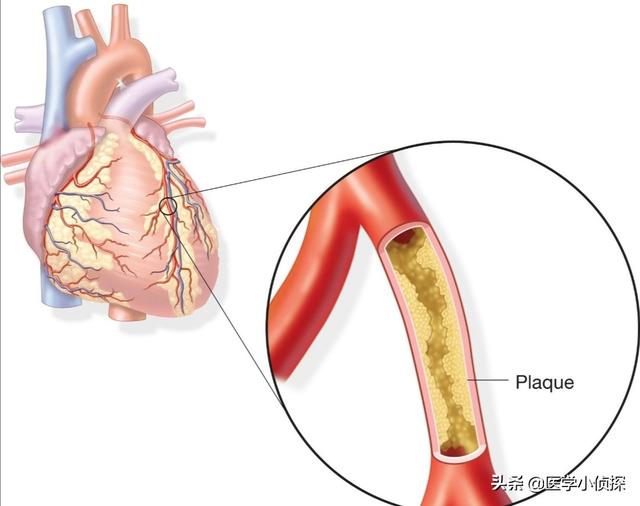

私たちは皆、多かれ少なかれ知っているはずだ。冠状動脈性心臓病とは、主に心臓の冠状動脈が狭くなる病気である。心臓に血液を供給する血管の狭窄は、心筋虚血や心筋壊死を引き起こす可能性があり、この狭窄を解消して冠動脈への血液供給を回復させるために、治療法のひとつは次のようなものである。何か支えとなるものを持っていく。それこそが、今、私たちが話しているブラケットなのだ。

冠状動脈は心臓に血液を供給する主な動脈で、年齢、三高、慢性病、悪習慣などの影響を受けて、心臓に血液を供給する冠状動脈も他の動脈と同じように、アテローム性動脈硬化症、狭窄、プラークなどの問題が現れる、冠状動脈の狭窄が50%以上の場合、通常、心臓の血液供給と酸素供給が大きな影響を受けると考えられ、このような場合、冠状動脈性心臓病と診断することができます。このような場合、冠動脈性心疾患と診断することができる。

(2) 動脈硬化:冠動脈性心疾患とは、血液中の脂質成分が内皮細胞の下に侵入し、炎症反応が起こり、動脈硬化性プラークが形成されることによって引き起こされる病気のことである。

- 冠動脈は、心臓そのものに血液を供給する動脈であり、動脈硬化、または私たちがよく呼ぶプラークである。冠動脈はプラークを生成し、プラークは徐々に大きくなり、心臓への血液と酸素が不足し、さまざまな症状を引き起こす。

冠動脈性心疾患とは、冠動脈アテローム性動脈硬化性心疾患の略称であり、主に心臓に血液を供給する動脈である冠動脈のアテローム性動脈硬化によって引き起こされる。動脈にアテローム性動脈硬化症が起こると、動脈の内表面にプラークが形成され、プラークが蓄積するほど動脈の直径が狭くなる。狭窄の程度が50%未満であれば、心筋への血液供給には影響しないので、一般的に症状はありませんが、50%以上になると、心筋への血液供給に影響を及ぼし、心筋の酸素消費量が増加しても、心筋が十分な酸素を得ることができず、心筋虚血、低酸素状態になると、胸部圧迫感、胸痛の症状が誘発され、これを狭心症と呼びますが、狭心症の症状は活動を停止すると徐々に緩和されます。狭窄の程度がさらに悪化したり、局所的なプラークの破裂、冠動脈の血栓閉塞によって心筋虚血が生じたりすると、狭心症の程度はさらに悪化し、緩和されない状態が続き、閉塞が解除されなければ心筋虚血壊死を引き起こし、ついには患者の突然死に至ることもあり、これが心筋梗塞と呼ばれるものです!